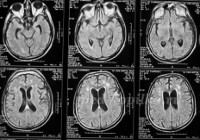

Сначала специалист оценивает все структуры головного мозга, полушария и желудочков. Определяется толщина белого вещества и структура коры, соотношение полушарий головного мозга. Их размеры сравниваются, указывается их расположение относительно центральной линии (индекса срединных структур). Размер переднего рога боковых желудочков взрослого человека обычно составляет от 12 до 15 в зависимости от возраста. Ширина третьего желудочка также оценивается. Исследование орбитальной области является важным этапом в МРТ: оценка структуры зрительных нервов, глазных сосудов, размера и положения глазных яблок. Исследование также позволяет определить размеры и положение внутреннего слухового канала. Кроме того, во время МРТ головного мозга мы изучаем анатомию мозжечка, ствола головного мозга и базальных ганглиев, а также эволюцию спинномозговой жидкости в сильвийском акведуке.

Наличие зоны потемнения может указывать на опухоль или кровоизлияние (травма, инсульт). Смещение центральных структур головного мозга свидетельствует о возможных образованиях в области внутримозговых структур или на границе с твердой мозговой оболочкой. В этом случае необходимо уделить особое внимание камерам для диагностики возможной внутричерепной гипертонии и выявления препятствий для нормального спинномозгового оттока жидкости. Гипофиз на МРТ обычно напоминает прямоугольник. В процессе интерпретации результатов исследования оценивается форма гипофиза, его размеры и расположение, наличие патологических образований в этой области. Когда часто наблюдаются опухоли гипофиза, синдром пустого турецкого седла или тяжелая гипоплазия гипофиза.